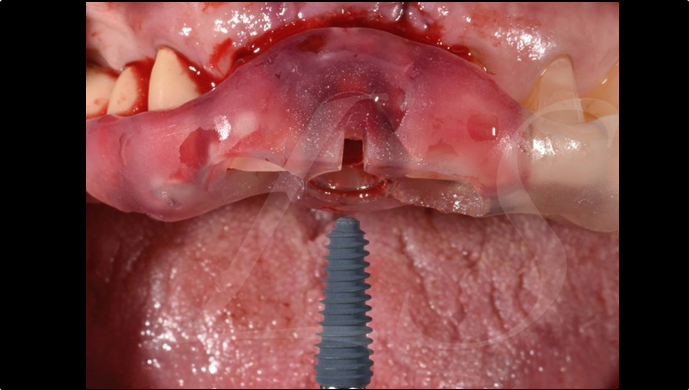

“Automated customized drilling protocols for optimum implant stability/ ONE-DAY implants ”

Clinical case: : Immediate loading of lower molars using R2Gate prefabricated 3D-printed provisional restoration

- Courtesy of Dr. Sam Omar, Egypt -

Dr.Sam Omar, immediate loading, digital guided surgery, digital ONE-DAY implant, maxillary anterior, #21, guided surgery, immediate loading, AnyRidge, R2GATE, Mega ISQ, MEG Torq, R2GATE Full Surgical Kit

implant system, R2GATE Guide, R2GATE surgical kit (AnyRidge), Mega ISQ